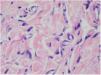

Punch biopsies of the skin lesions were performed, which showed a normal epidermis and fibrohistiocytic proliferation with small vessels in the reticular dermis, displaying lumen vessels filled with prominent endothelial cells, involved with a perivascular inflammatory response composed by multinucleated histiocytic cells (MCs) and a few plasma cells. In the papillary dermis, fibroblastic proliferation and thickened collagen fibers were found (Figs. 2 and 3) and numerous bizarre MCs with scalloped margins were found in the adjacent dermis. The immunohistochemical (IHC) panel performed found the following: S-100 protein (negative), FXIIIa (positive) in MCs, CD68 (positive) in MCs, CD34 and CD31 (positive) in small vessels, and CD4 (positive) in dermal lymphocytes (Figs. 4 and 5). The final diagnosis was established as compatible with multinucleate cell angiohistiocytoma. Due to the benign nature of the illness, the patient chose not to undergo treatment.

The main histopathological finding in MCAH is the proliferation of venules and capillaries in the dermis, accompanied by lymphocytic infiltrate and angular multinucleated cells. These cells may exhibit up to ten hyperchromatic nuclei and have basophilic cytoplasm; the cells express vimentin and factor XIIIa, and there is dermal fibrosis and sparse lymphohistiocytic infiltrate.2,7,10